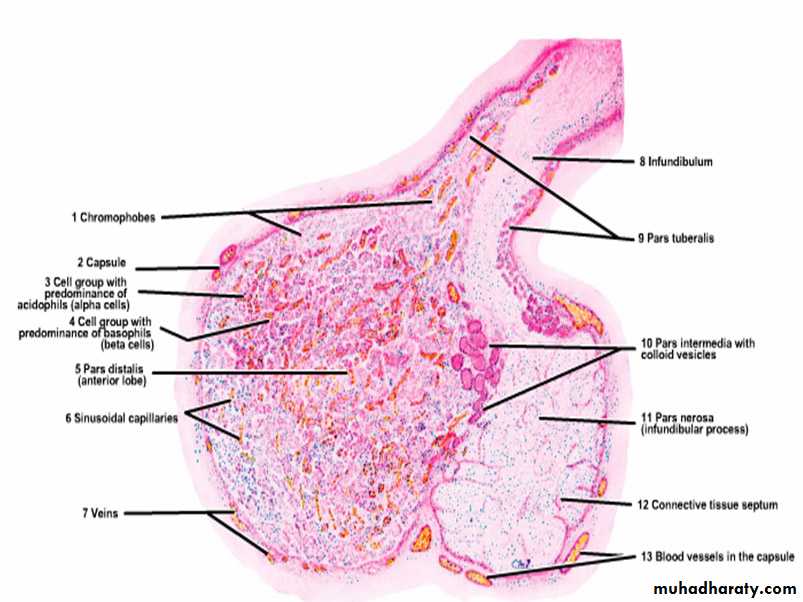

Hypophysis: pars distaiis, pars intermedia, and pars nervosa. Stain: mallory-azan & orange G.